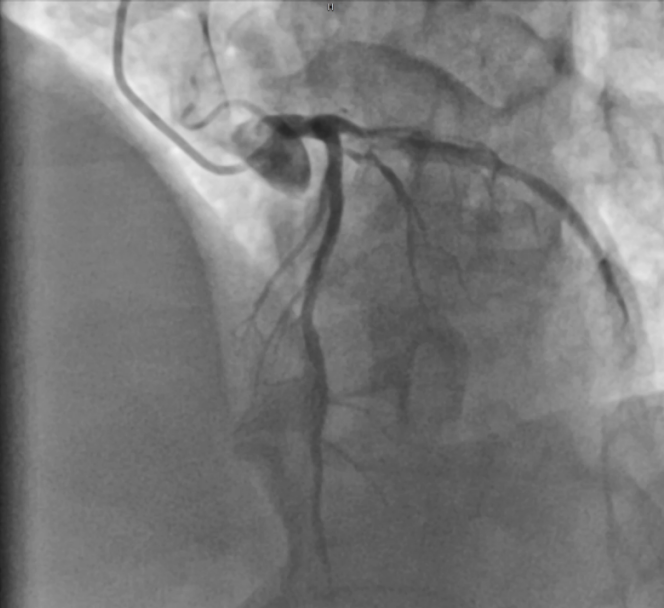

左冠造影结果

此次手术的患者为61岁男性,主因活动后胸闷、胸痛8年余,加重半月入院。患者8年前有急性心梗病史,分别于前降支及右冠植入3枚支架。此次入院造影可见右冠近端支架通畅,中至远段弥漫性狭窄,最重85%,后降支远段节段性狭窄60%。左主干无异常,前降支支架通畅,回旋支近端节段性狭窄80%。